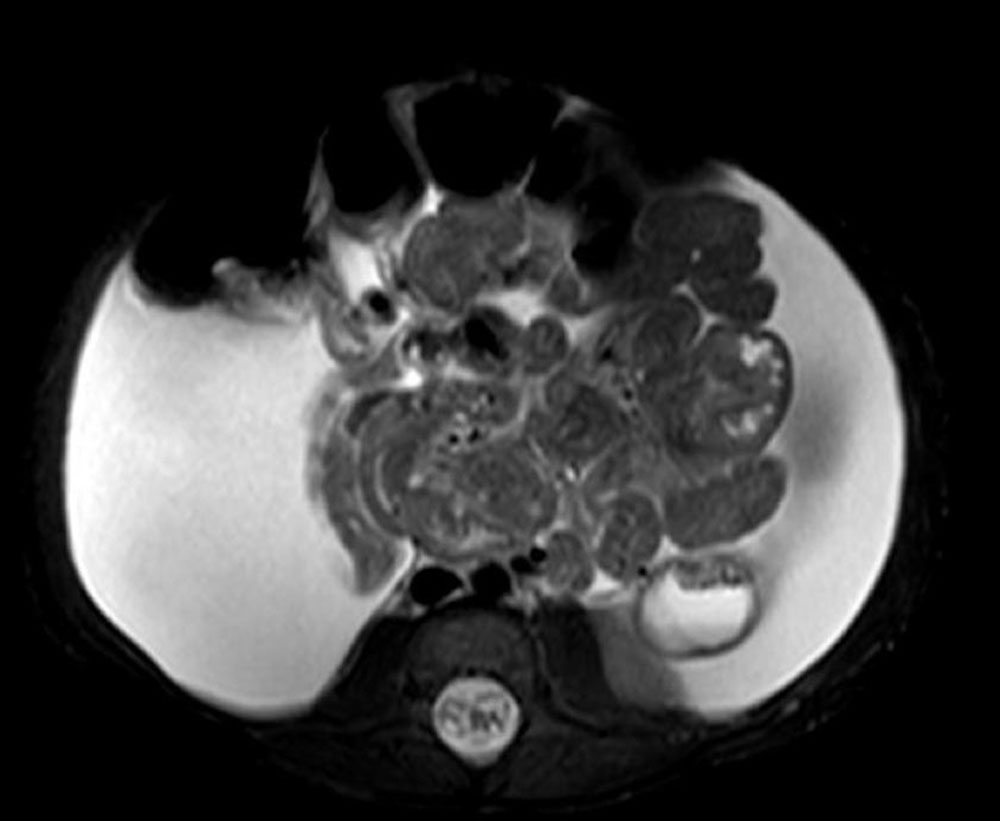

One lymphatic malformation in children that involves the abdomen is Central Conducting Lymphatic Anomaly (CCLA). This is defined as inadequate central drainage of the major trunk lymphatics due to dysmotility, stenosis, or aplasia of the main central abdominal and/or thoracic lymphatic ducts. Insufficient drainage due to congenital malformations of the thoracic duct or cisterna chyli results in lymphostasis with consecutive peripheral lymphatic hypertension and reflux in various organ systems, depending on the location of the drainage obstruction. In this context, thoracic lymphatic hypertension can lead to pulmonary lymphatic hypertension with recurrent chylous pleural effusions or lymphatic congestion of the lungs with plastic bronchitis. Abdominal outflow obstruction (e.g., dysplasia or aplasia of the cisterna chyli) can result in protein-losing enteropathy, chylous ascites, abdominal lymphatic cysts, and/or reflux and retention of lymphatic fluid into one or both extremities (lymphedema of the leg) or the genital region. The pent-up lymphatic pressure can in turn lead to leakage of lymphatic fluid through the skin (lymphorrhea) or cutaneous lymphatic vesicles. Intranodal lymphangiography with ethiodized poppy seed oil injection into a punctured lymph node in the inguinal region can be very helpful in diagnosing this serious condition.